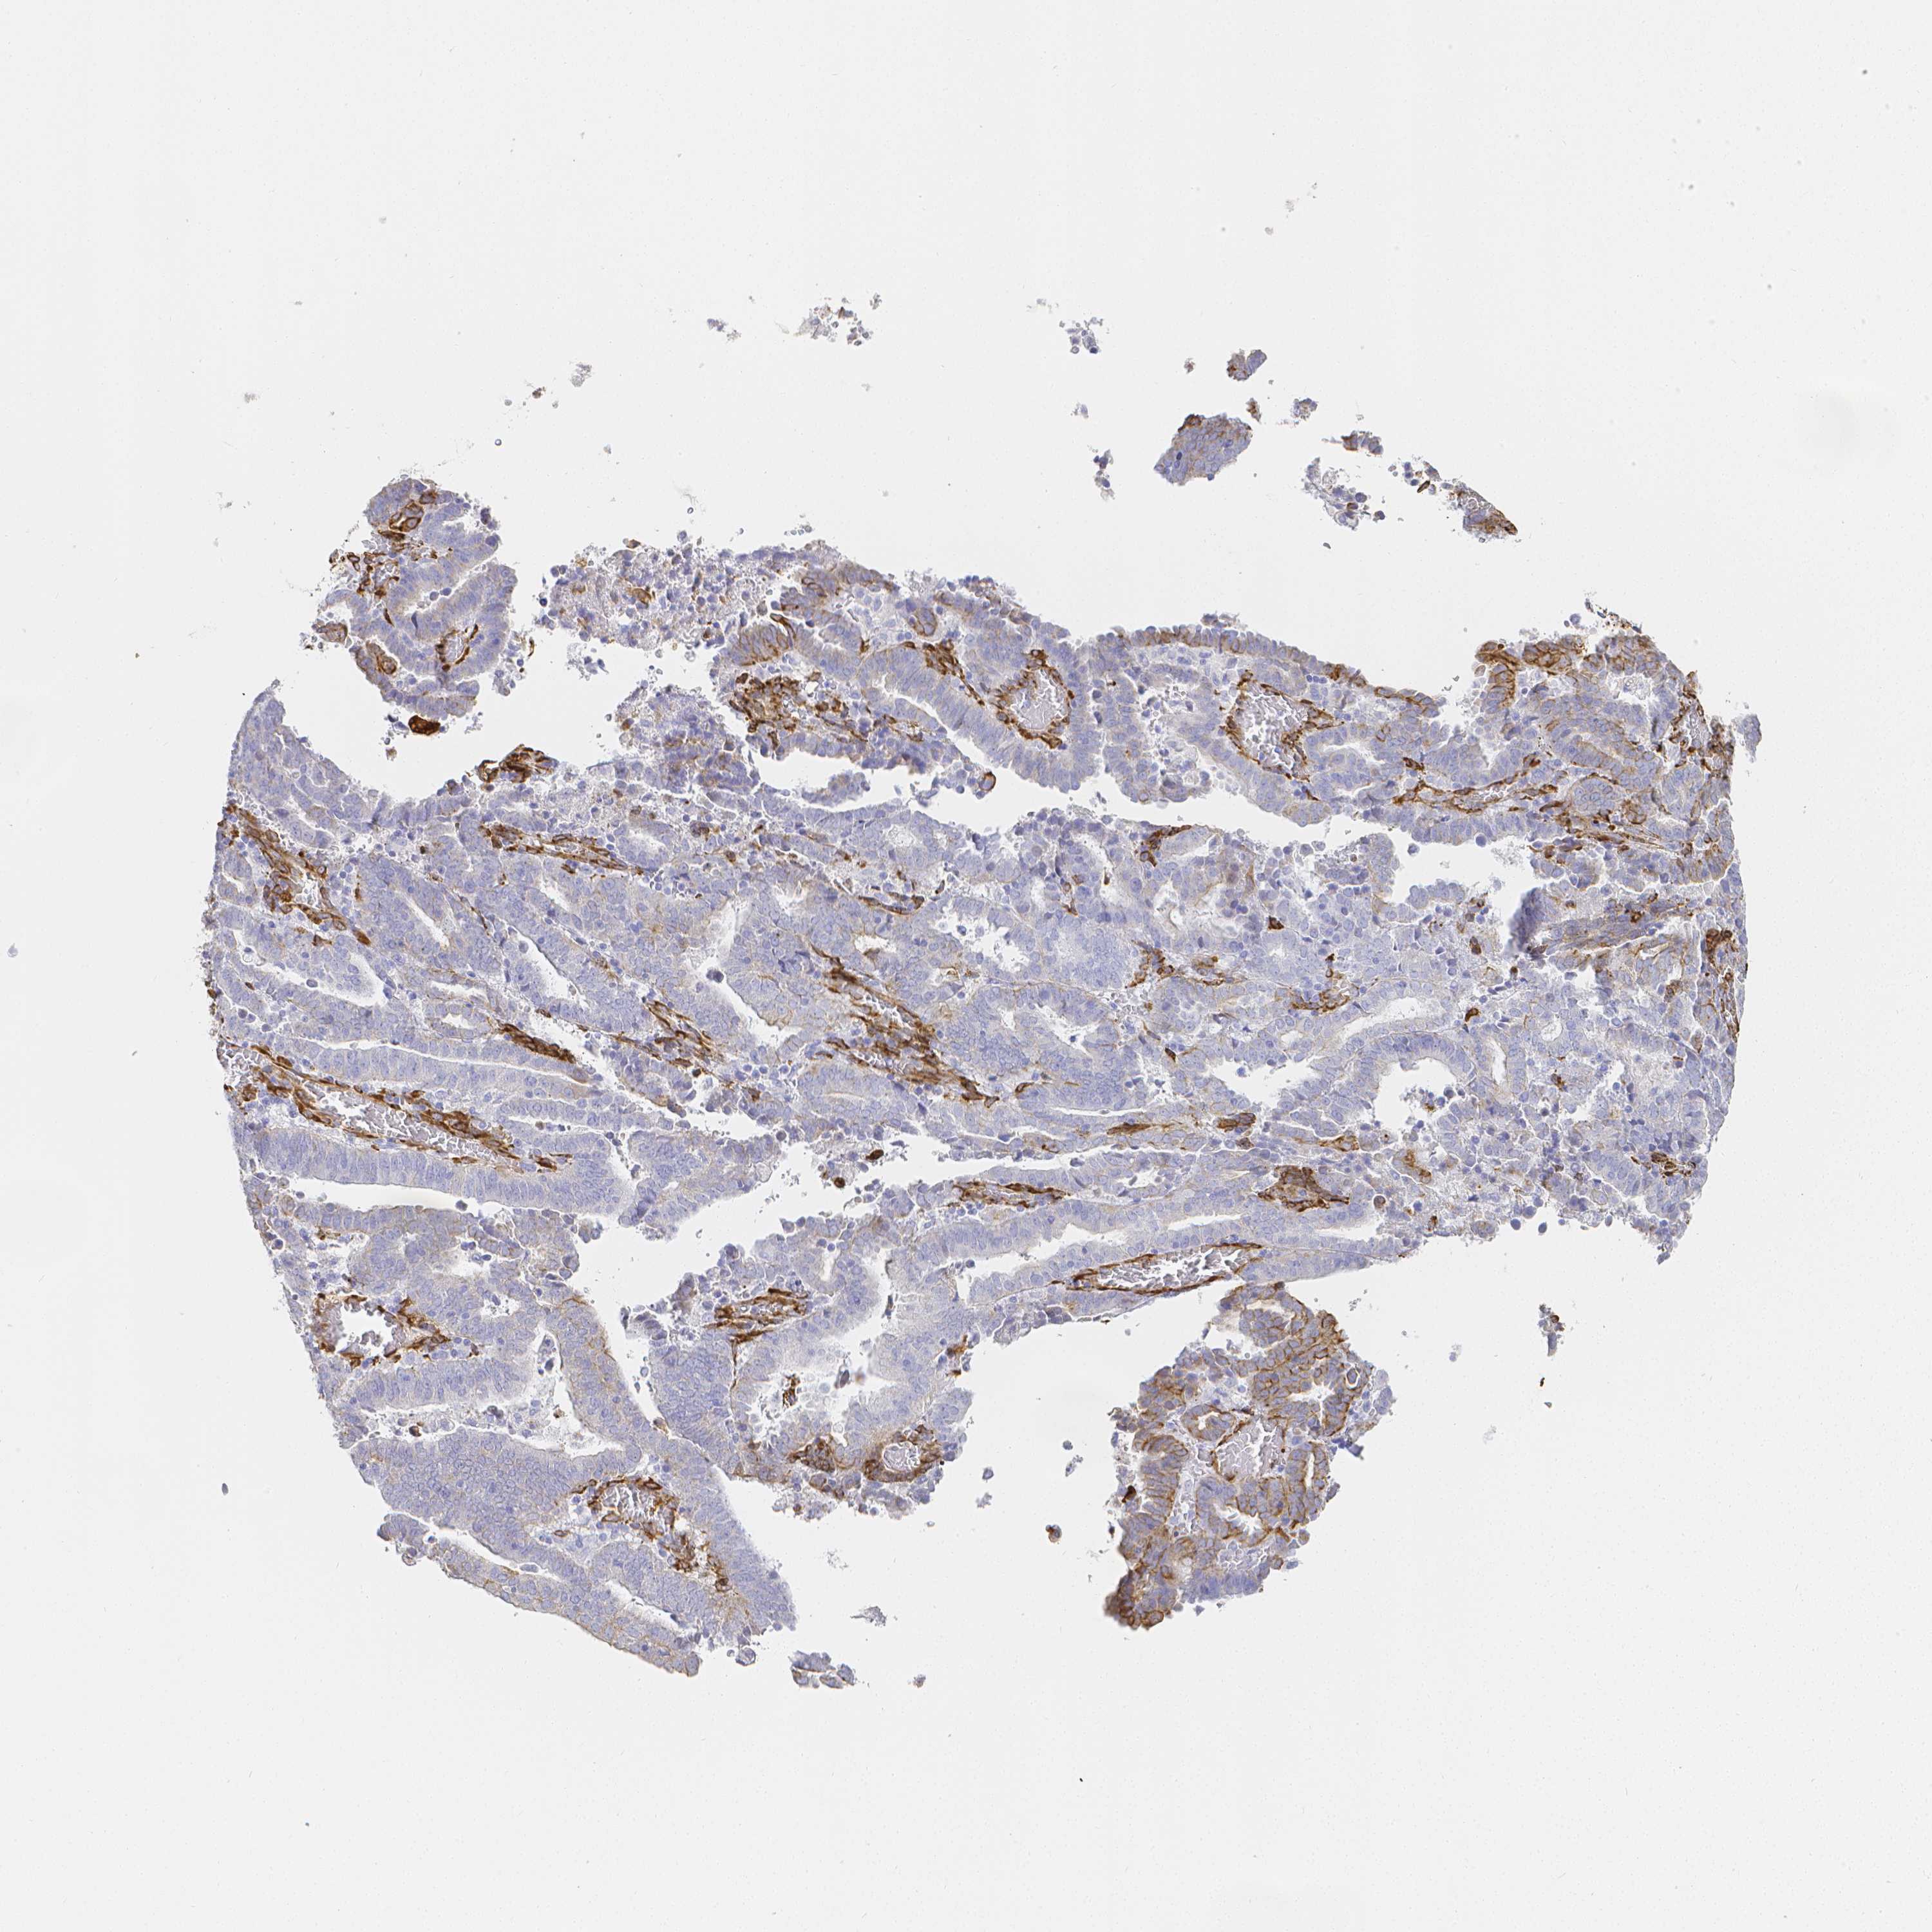

ENDOMETRIAL CANCER - Protein expressioni

A mouse-over function shows sample information and annotation data. Click on an image to view it in a full screen mode. Samples can be filtered based on level of antibody staining by selecting one or several of the following categories: high, medium, low and not detected. The assay and annotation is described here.

Note that samples used for immunohistochemistry by the Human Protein Atlas do not correspond to samples in the TCGA dataset.

Antibody stainingi

Antibody staining in the annotated cell types in the current human tissue is reported as not detected, low, medium, or high, based on conventional immunohistochemistry profiling in selected tissues. This score is based on the combination of the staining intensity and fraction of stained cells.

Each image is clickable and will lead to virtual microscopy that enables deeper exploration of all samples and also displays staining intensity scores, fraction scores and subcellular localization as well as patient and tissue information for each sample.

Antibody HPA055245

Staining

High

Medium

Low

Not detected

Intensity

Strong

Moderate

Weak

Negative

Quantity

>75%

75%-25%

<25%

None

Location

Nuclear

Cytoplasmic/membranous

Cytoplasmic/membranous,nuclear

Adenocarcinoma, NOS

Adenocarcinoma, metastatic, NOS